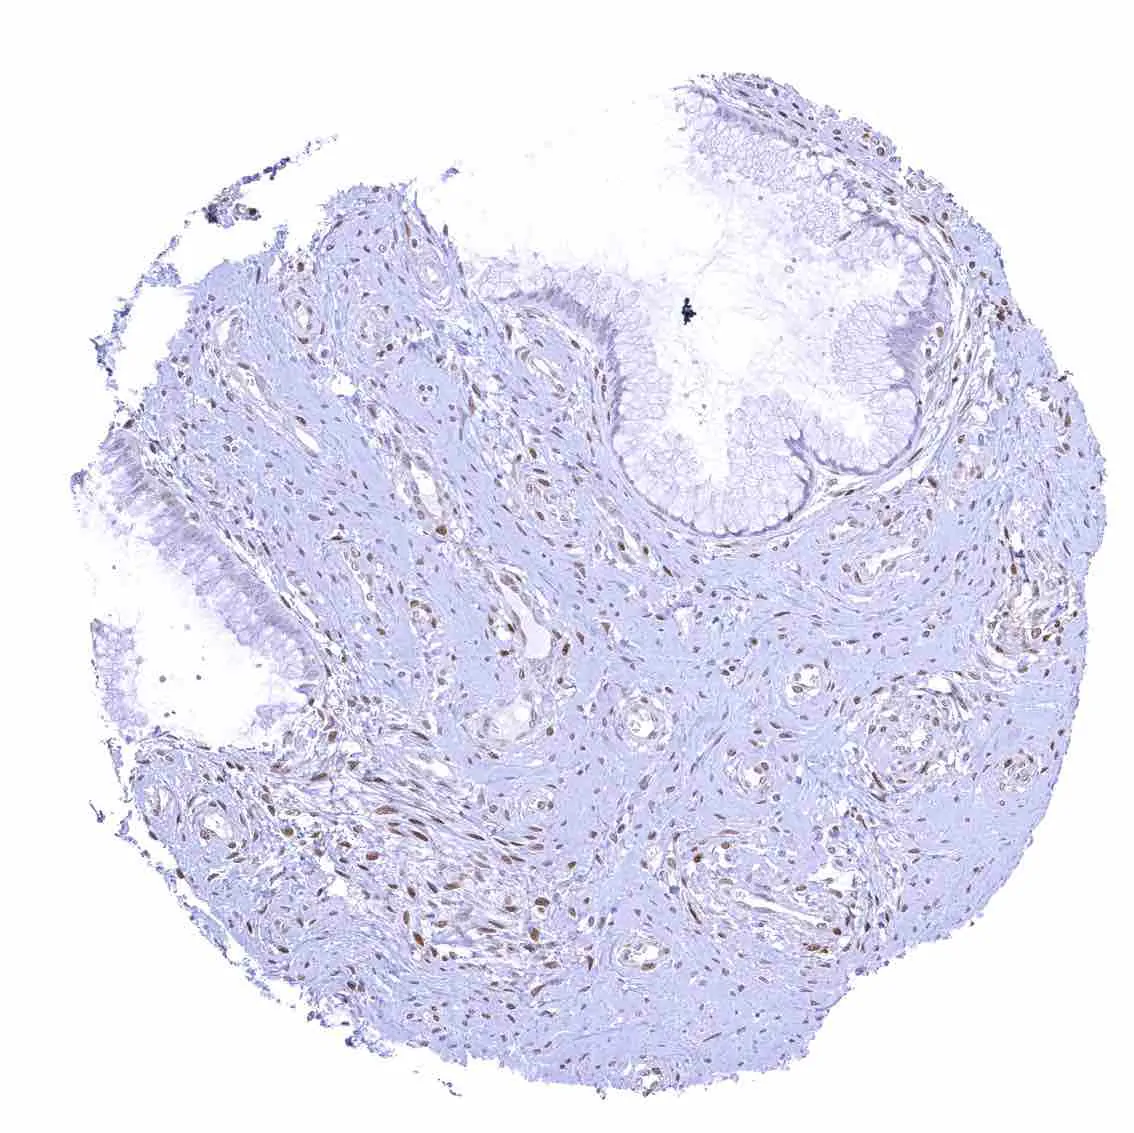

Uterus, ectocervix – Nuclear staining of squamous epithelial cells predominates in the more mature cell layers (top 50_ of the epidermis).

Uterus, endocervix – Nuclear p27 staining is variable in the endocervix. It is positive in all epithelial cells in this sample.

Uterus, endocervix